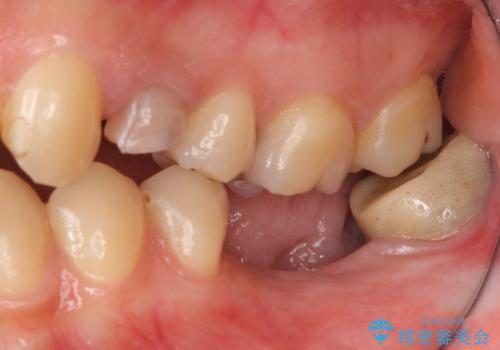

右下は虫歯がひどく、抜歯が必要でした。また、右下の一番奥の歯は親知らずのため使うことができない状態でした。

右上に部分矯正を行い、クリアランスを確保した後、右下にイプラントを2本埋入しています。

上の歯が伸びだしてきていたため、部分矯正を行い歯を移動させてから、向かい合わせの歯にインプラント治療を行っています。

右上第一大臼歯は六本木院の林院長に根管治療をお願いしました。